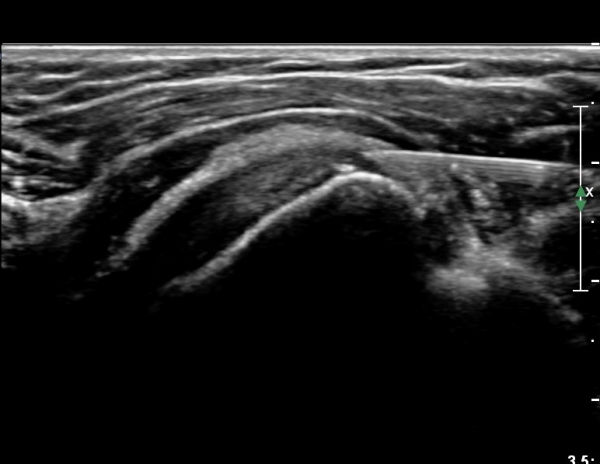

°ß°©ÇÏ±Ù°Ç ÇϺΠÁ¾´Ü¸é°Ë»ç¿¡¼­ °ß°©Çϱٰdz»  ÀÛÀº ¼®È¸È­ µ¢¾î¸®°¡ °üÂûµÈ´Ù(»çÁø 3, 4).